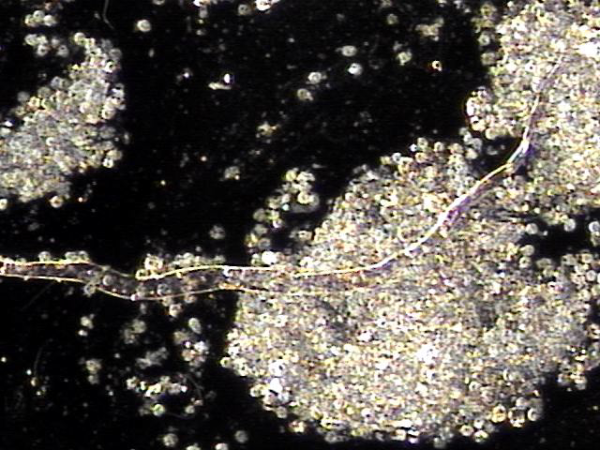

전립선의 주 3회 표적치료후 전립선관과 사정관, 그리고 정관등에 막혀 있던 섬유소 덩어리의 치료된 현미경학적 자료입니다.

This is a microscopic image of treated fibrin clumps that were blocking the prostatic ducts, ejaculatory ducts, and vas deferens, following targeted therapy on the prostate three times a week.